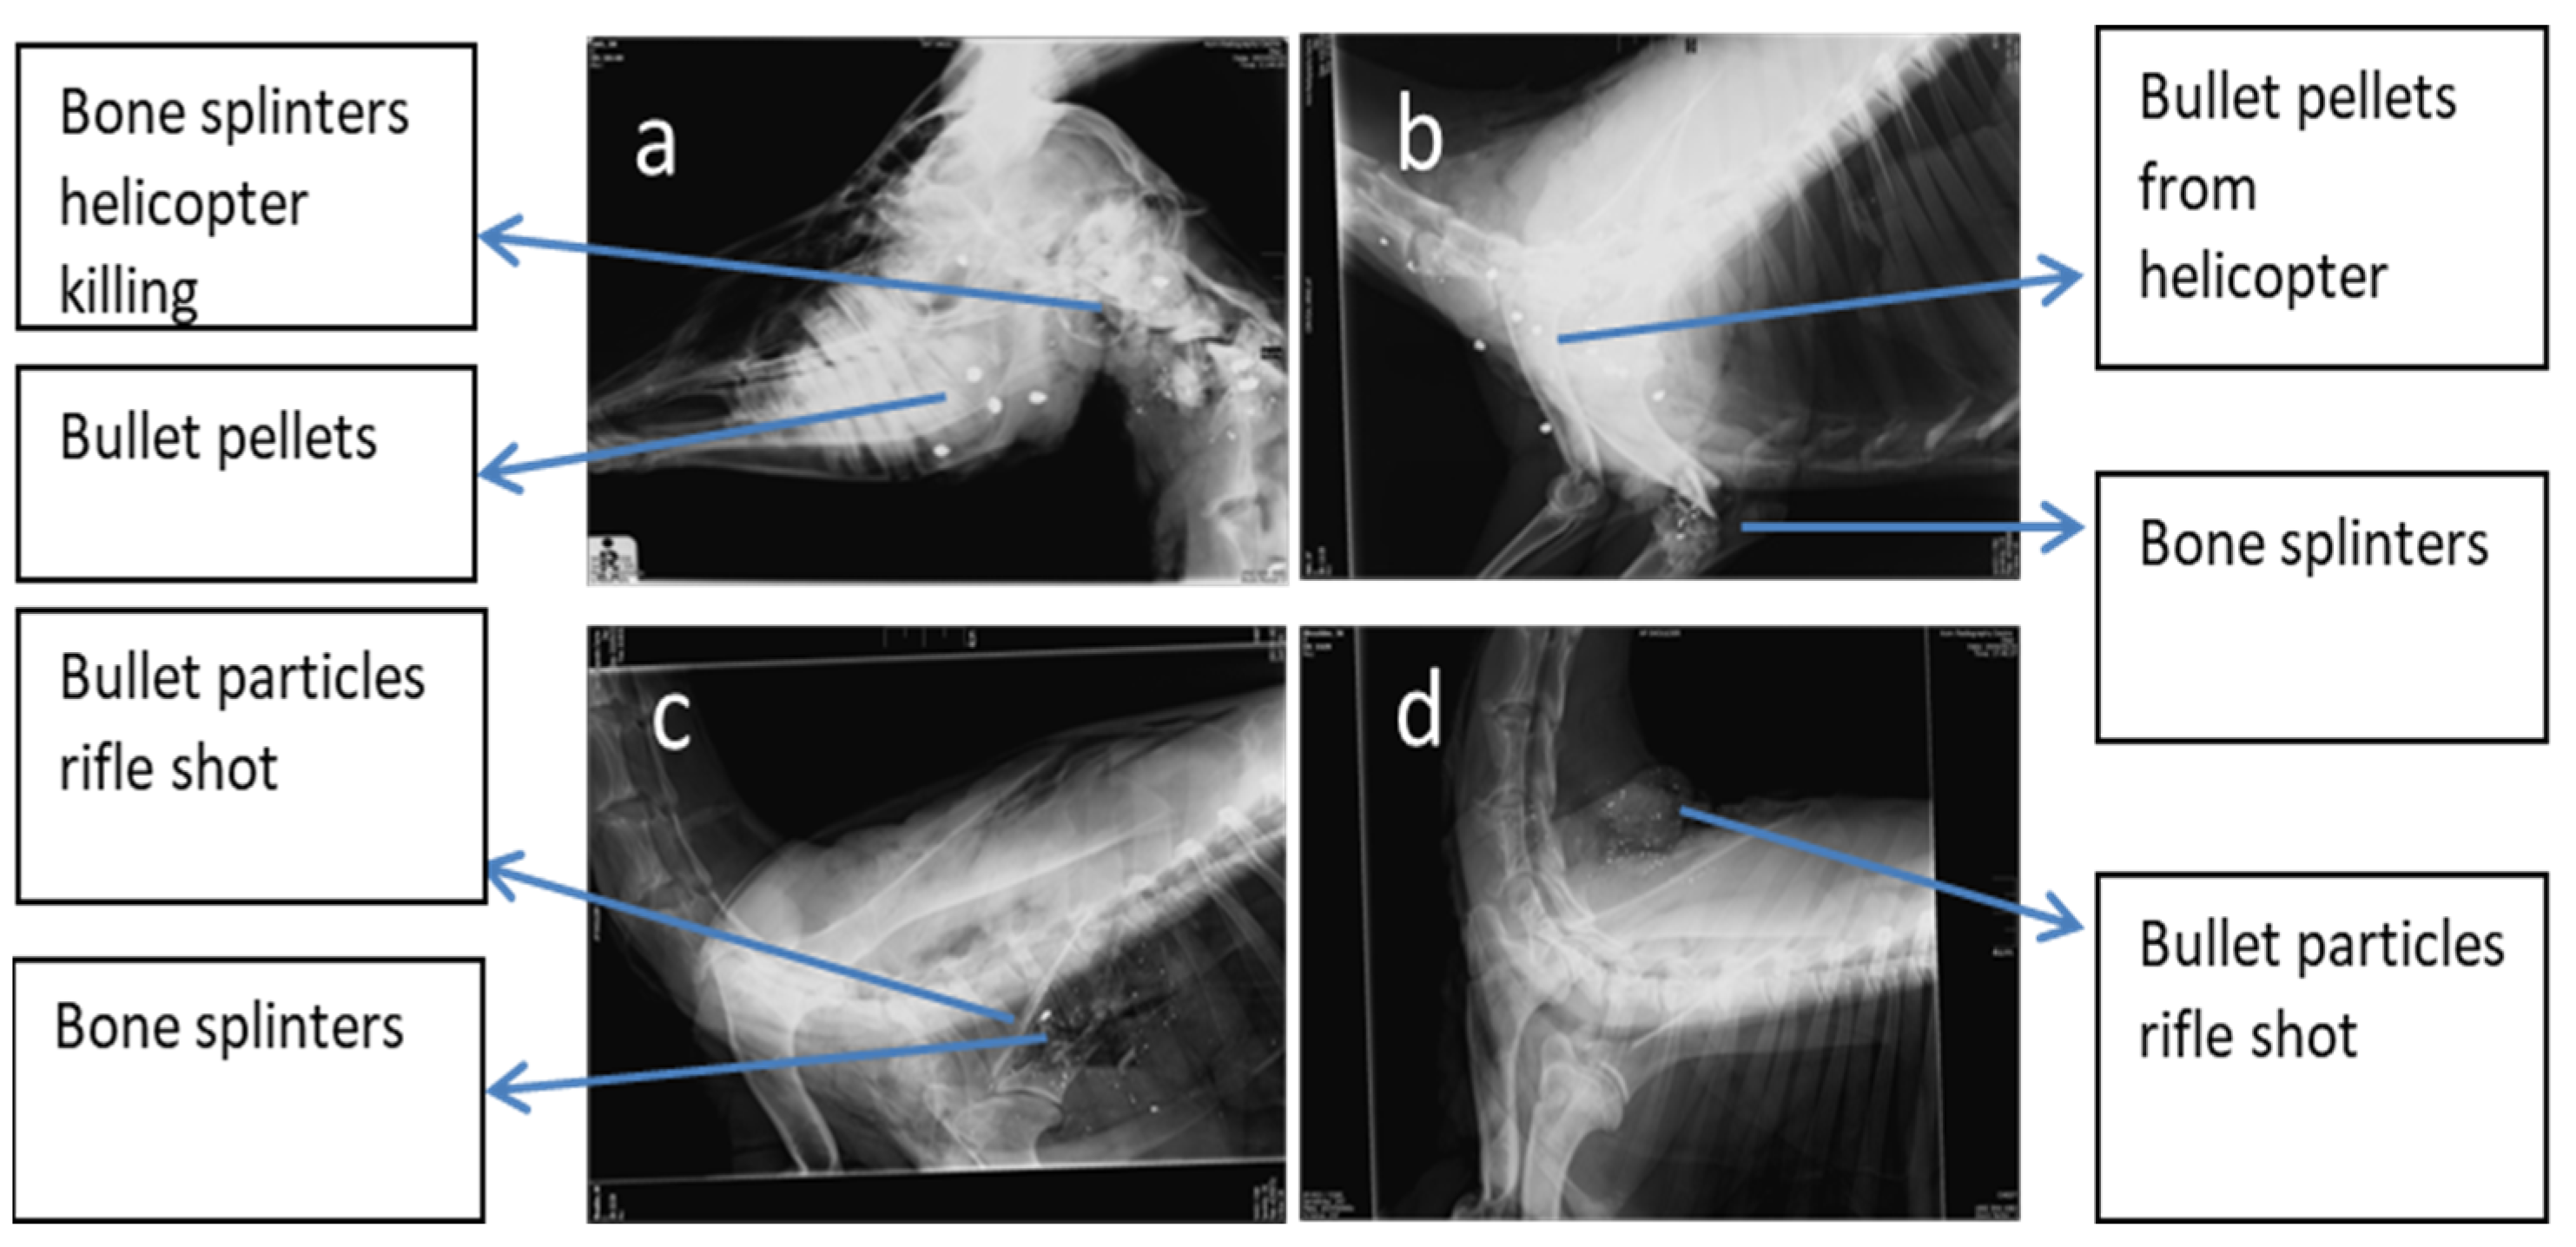

3.1. Impact and Dispersion of Physical Hazards

3.2. Particle Sizes of Bone Splinters and Bullet Fragments